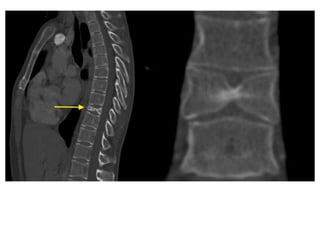

Sagittal CT image of a patient

with neck pain after lifting a

heavy object.

Shows fracture of spinous

process of C7 vertebra.

• 91.

Sagittal CT imageof a patient with neck pain after lifting a heavy object. Shows fracture of spinous process of C7 vertebra.